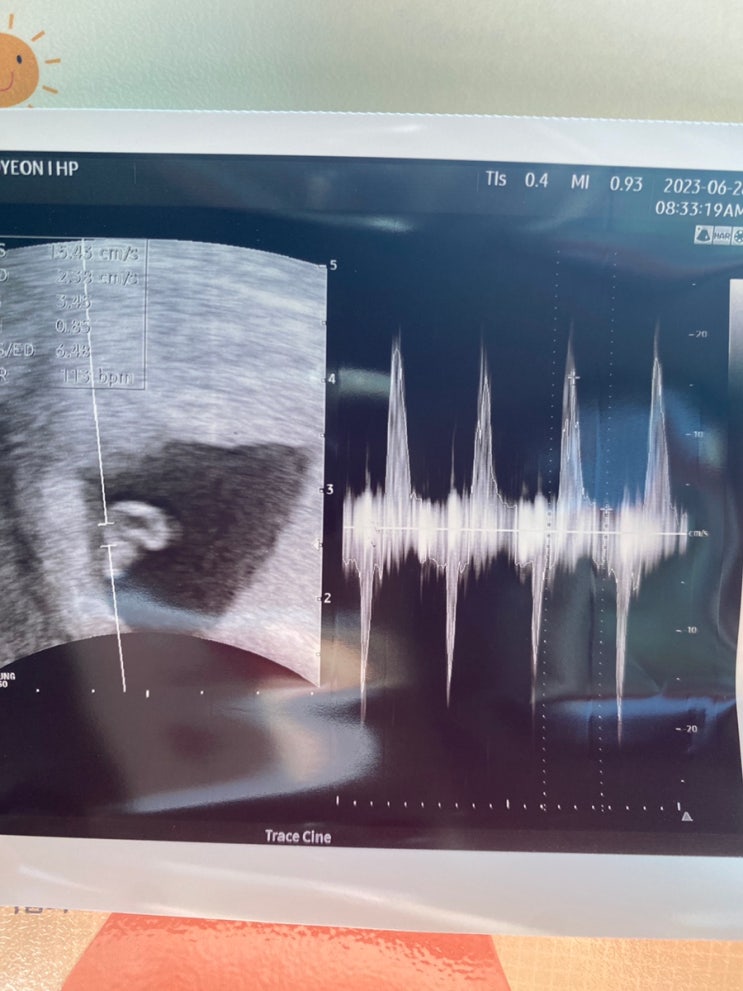

21주에 정밀초음파 이후 지금까지 소소한 이벤트들이 발생중.. 위장병으로 일주일간 고생하다 결국 약처방...

21주 정밀초음파 후기, 초산모 태동 언제부터?!

지난 16주 진료를 포스팅 할수 없었다...ㅠㅠ 간호사쌤 실수로 영상이 녹화되지 않았고.. 촘파 사진도 달랑...